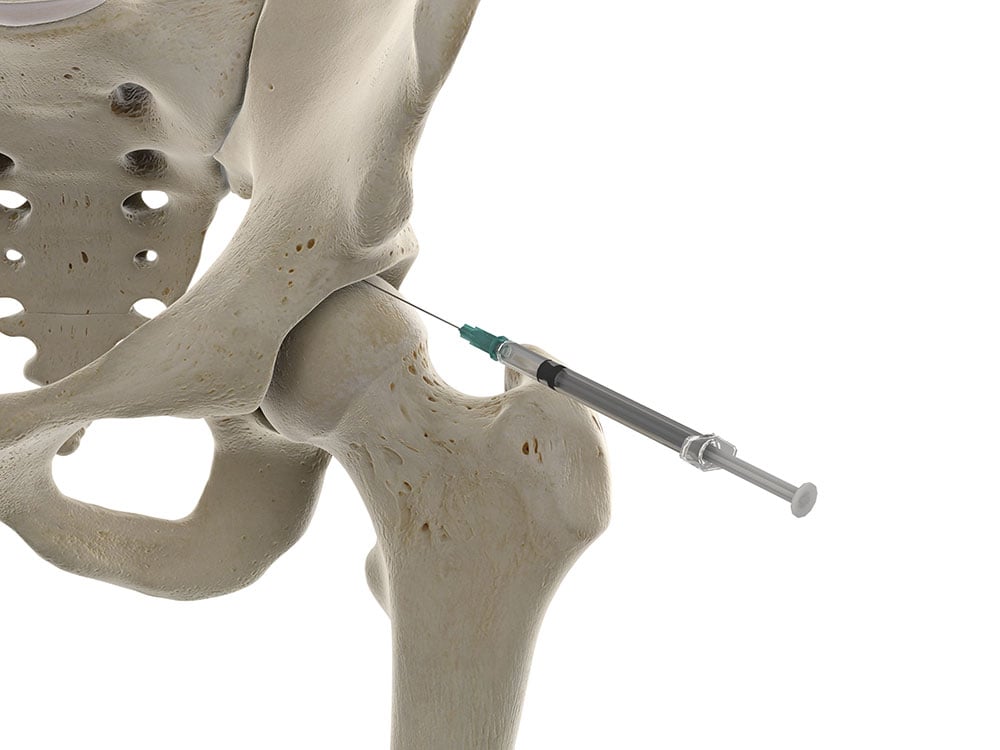

Intraarticular Hip Injection—Anterior Approach Ultrasound Guidance Cortisone Injection In Hip Using Ultrasound They can help relieve pain and inflammation in a specific area of your body. Your injection will be made up of a local anaesthetic and a steroid. Whether it be for the shoulder, hip, knee or frankly any other body part, studies overwhelmingly point to use ultrasound. Ultrasound guided injections play a valuable role in treating hip joint pain and. Cortisone Injection In Hip Using Ultrasound.